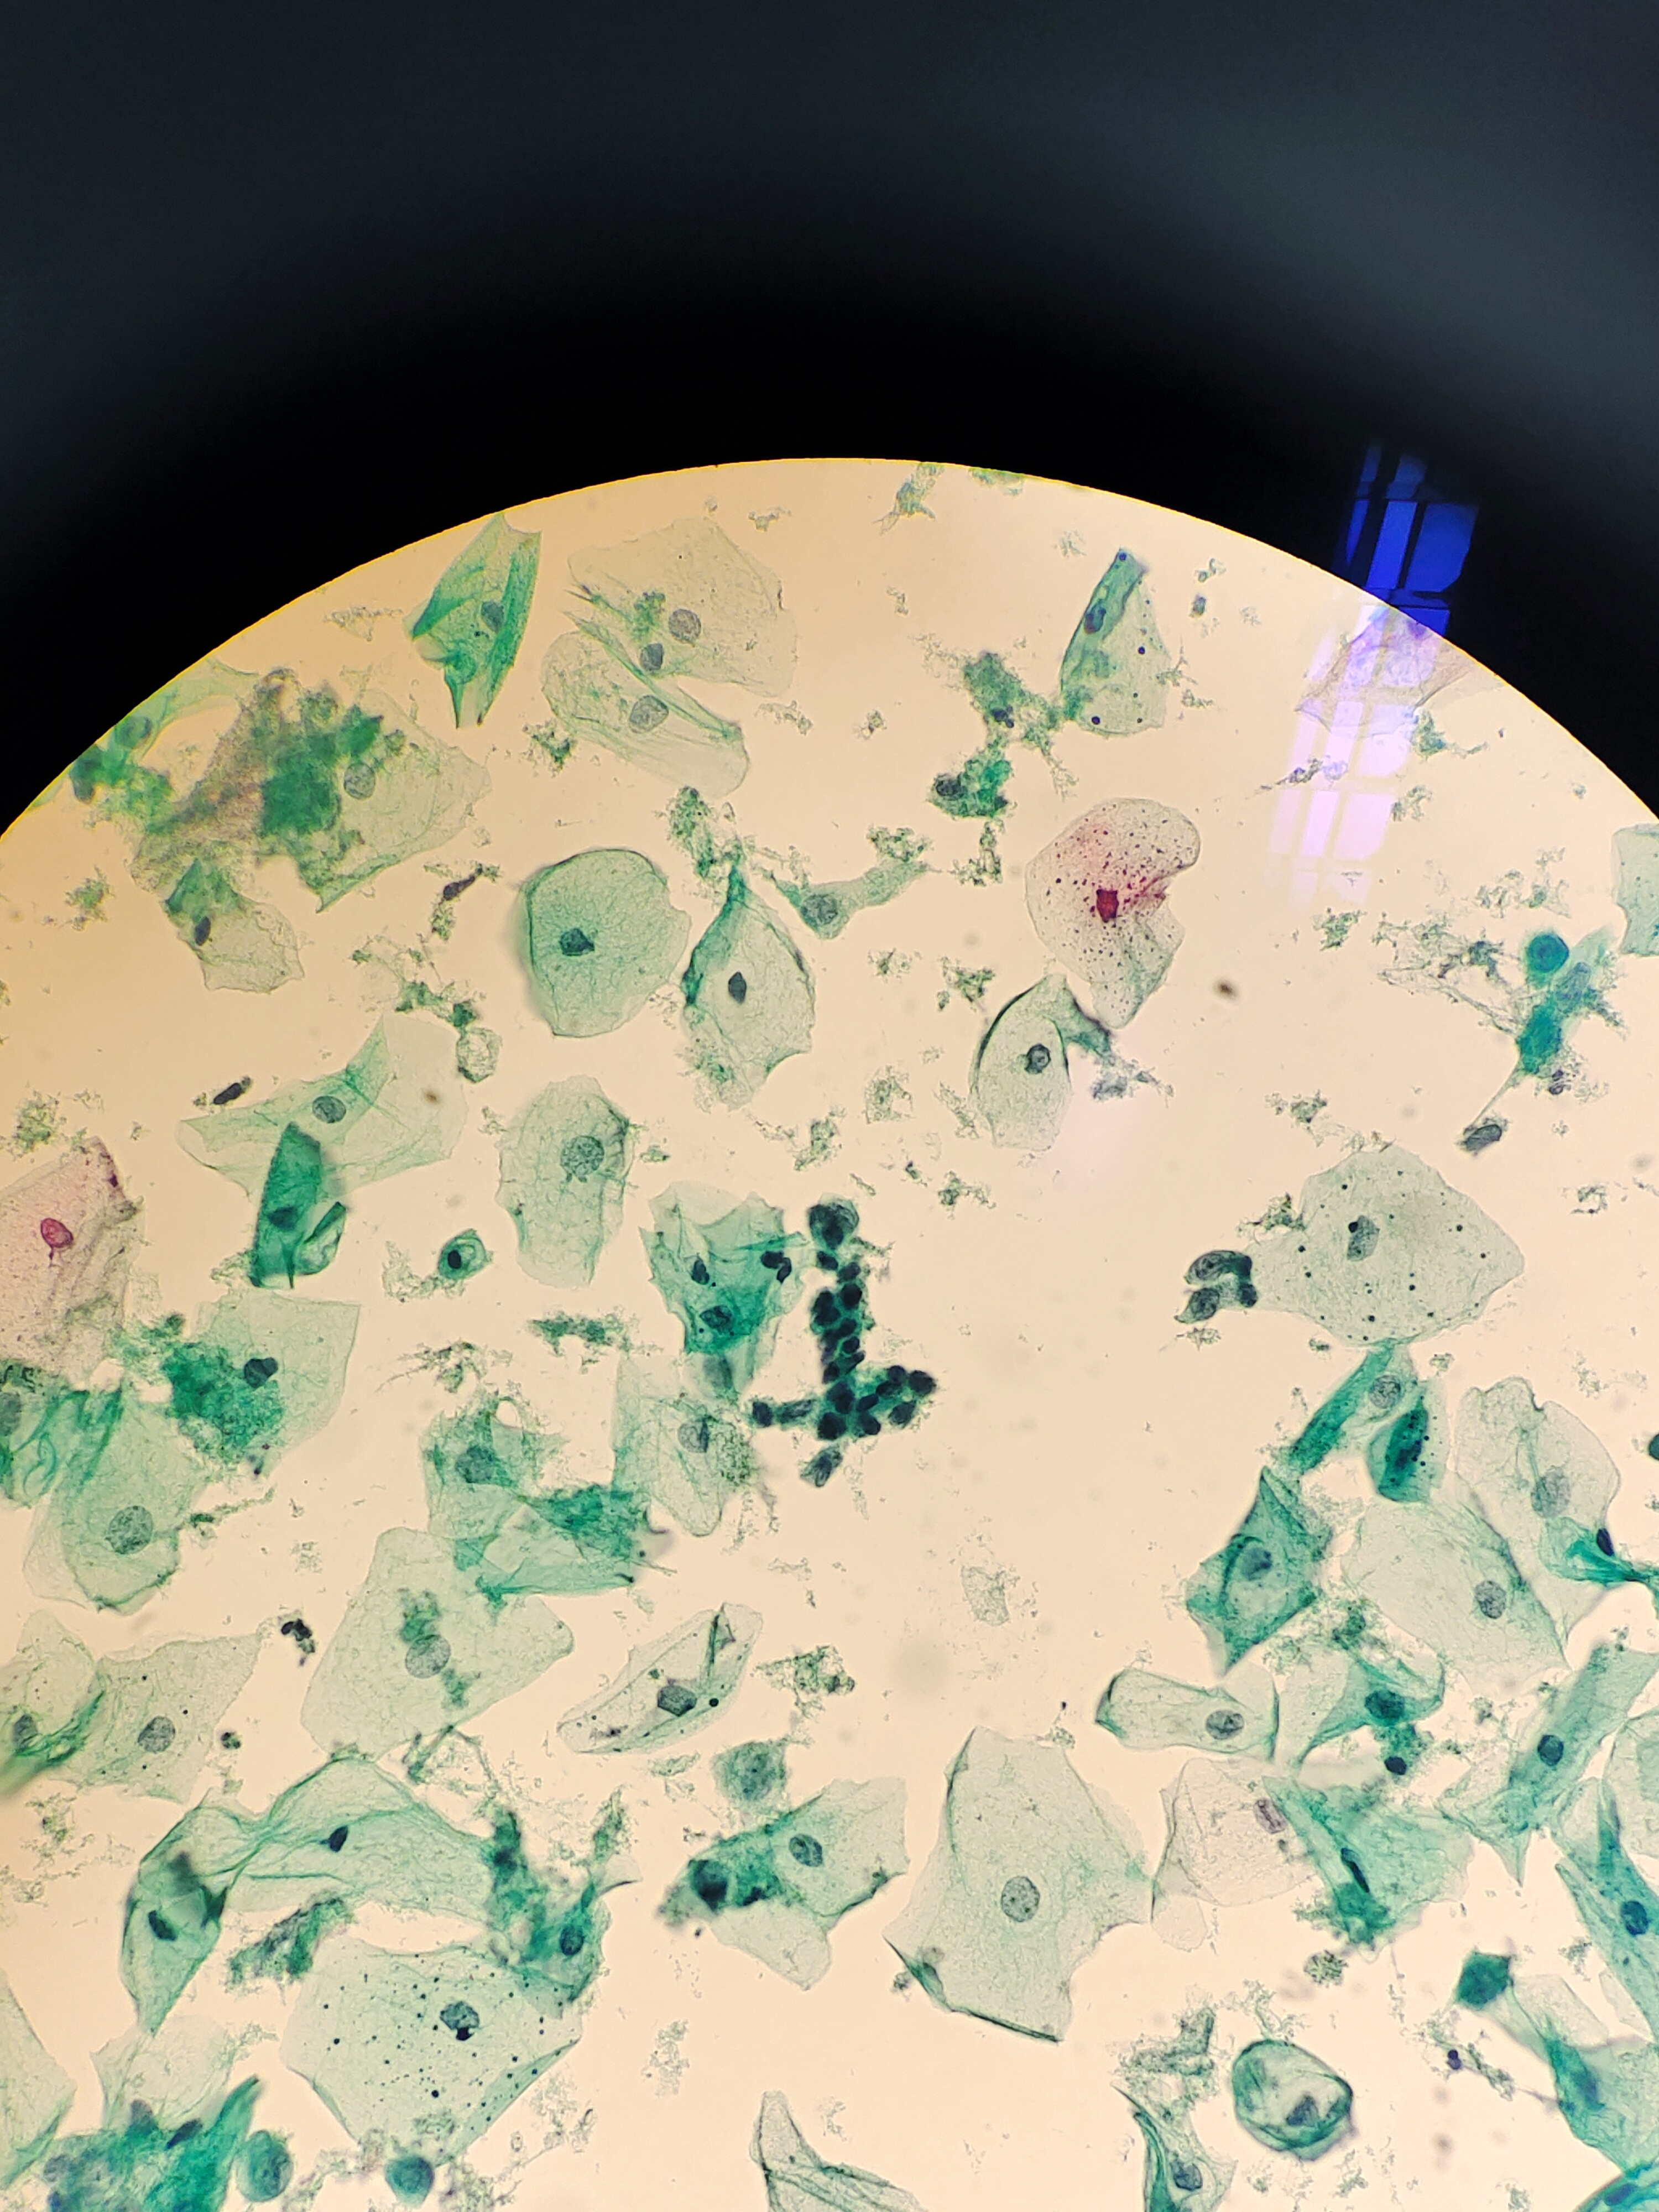

性别

女

年龄

77岁

一般病史

绝经20多年,阴道出血3天。HPV阴性。老师们,细胞不萎缩,有些核深染细胞,有事吗?

标本类型

宫颈

制片方法

液基

染色方法

巴氏

图1